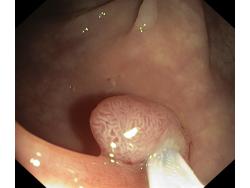

Polipy